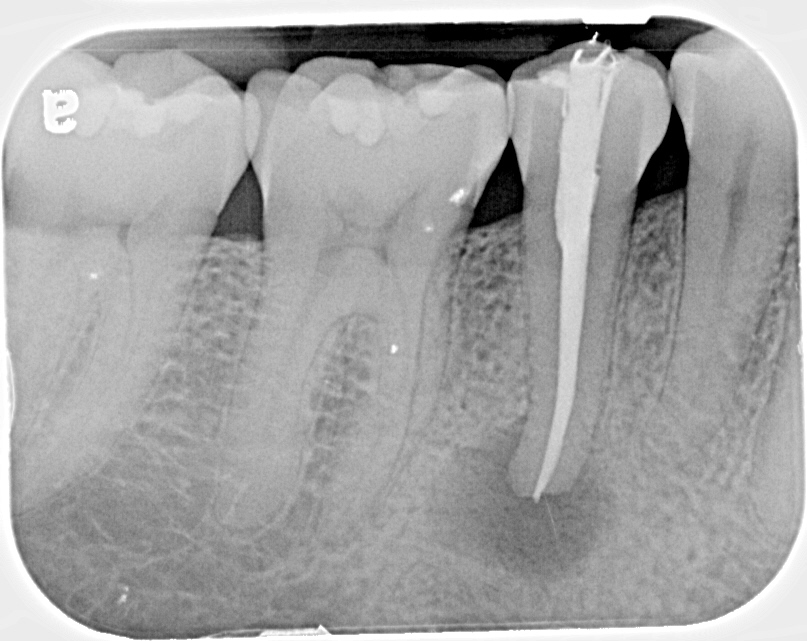

Prima di tutto bisogna stabilire che le radiografie dentali sono d'importanza cruciale per diagnosticare qualsiasi problema dentale e gli effetti potenzialmente pericolosi dei raggi X non dovrebbero tenere nessuno lontano dai controlli del dentista. É chiaro che i benefici delle radiografie hanno una maggiore importanza rispetto ai rischi che si possono incorrere, poiché le radiazioni delle radiografie dentali sono emesse a un dosaggio bassissimo. Per parlare in termini tecnici, un esame di routine che include 4 bitewing é di circa 0.005 mSv, che é meno delle radiazioni naturali giornaliere alle quali siamo normalmente esposti, inoltre questo dosaggio é lo stesso che subiamo quando prendiamo l'aereo per un viaggio di 1-2 ore. Quello che rimane un dato di fatto incontestato é che le malattie dei denti e dei tessuti circostanti possono essere controllati dal vostro dentista in modo accurato solamente a seguito di un esame radiologico dentale. Ecco alcuni problemi che possono diagnosticare i raggi X:

- carie al dente o presente nell'otturazione sottostante,

- infezioni alle ossa

- malattie periodontali